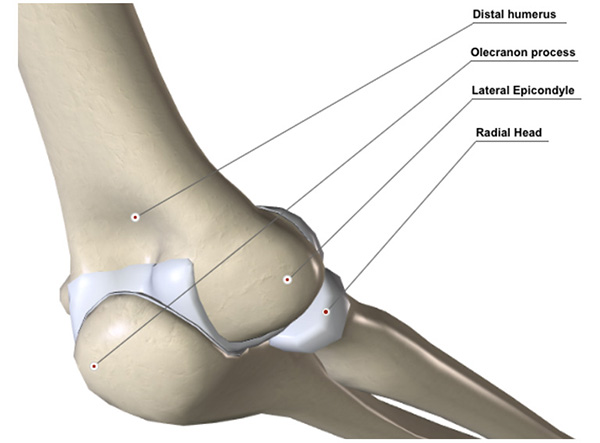

The elbow comprises three joints: the main hinge is between the trochlea of your humerus and the socket of your ulna.  Rotation of your forearm is achieved at the junction between capitellum and radial head (see diagram). The third joint between your upper ulna and upper radius also allows rotation.  The depth of your socket, the elbow ligaments, muscles that cross the elbow and the capsule all contribute to stability.  The elbow can be injured by direct force (e.g. landing on tip of your elbow) or by indirect force (e.g. landing on your hand)

Figure 2 View from the back of your elbow